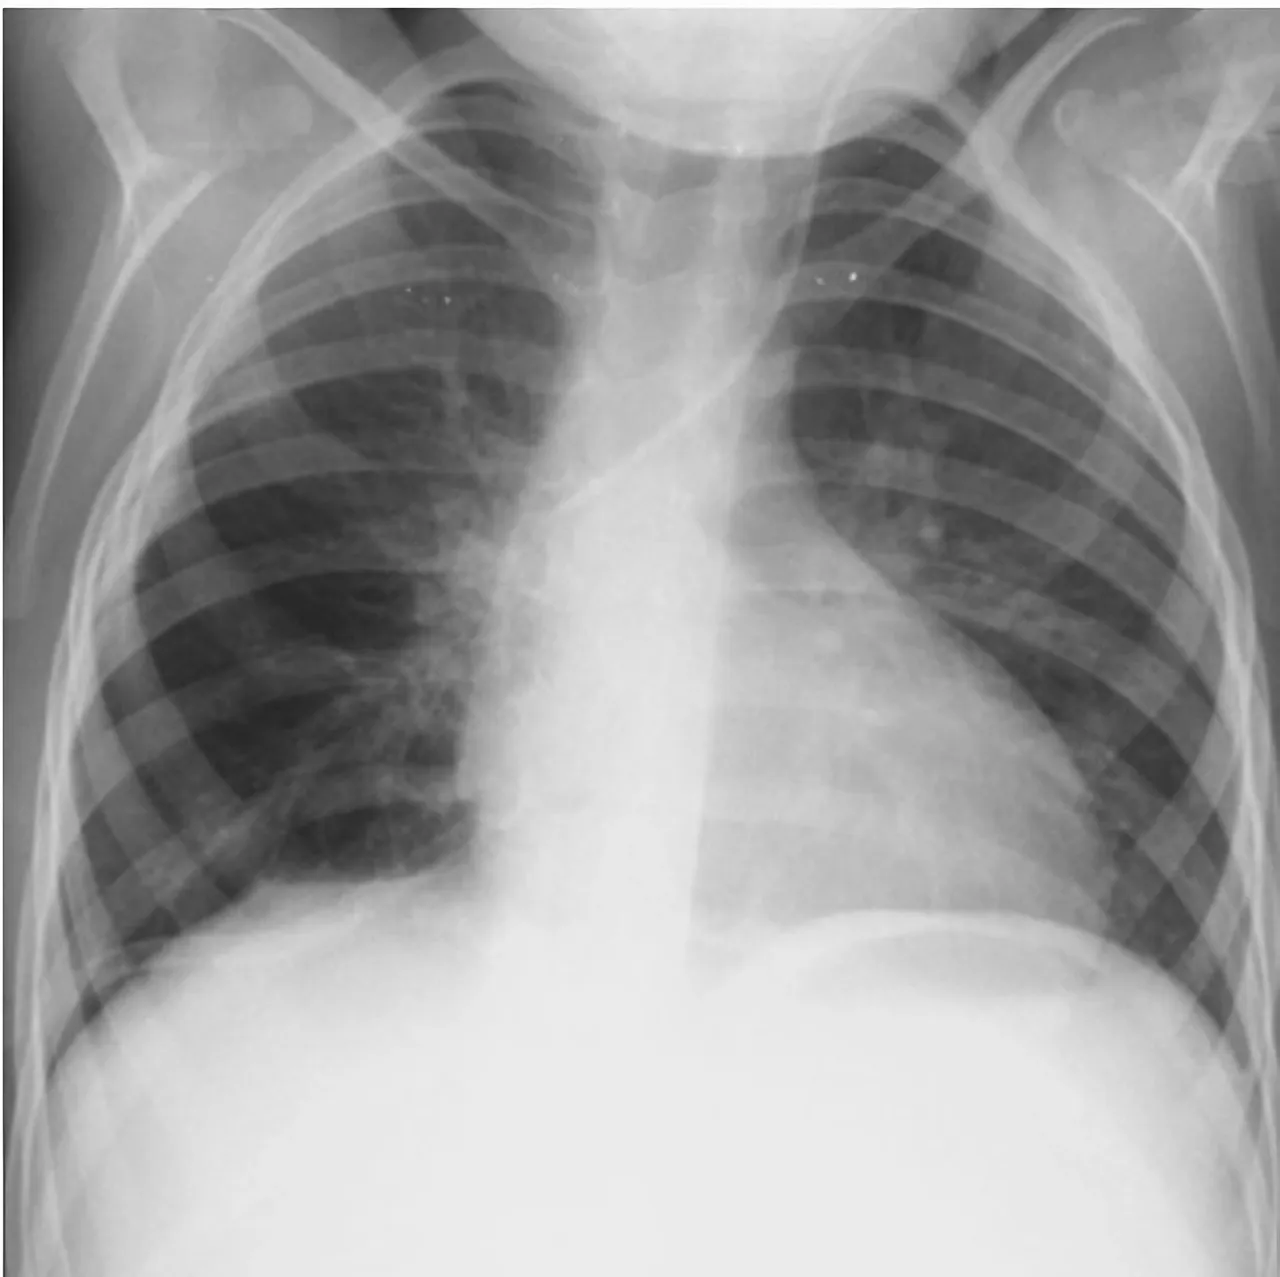

Investigațiile imagistice efectuate în cadrul serviciului de radiologie și medicină nucleară au arătat o situație gravă: o formațiune tumorală de aproximativ 12 x 9 x 10 cm, localizată în hemitoracele drept. Potrivit medicilor, tumora ocupa circa 80% din cavitatea pleurală, comprimând aproape în totalitate plămânul drept și exercitând presiune severă asupra structurilor mediastinale.

Evoluția postoperatorie a fost favorabilă. Pacienta a fost extubată în prima zi după intervenție, iar radiografia toracică din a doua zi postoperator a confirmat reexpansiunea completă a plămânului drept, fără semne de revărsat pleural. Tubul de dren a fost suprimat după 48 de ore.